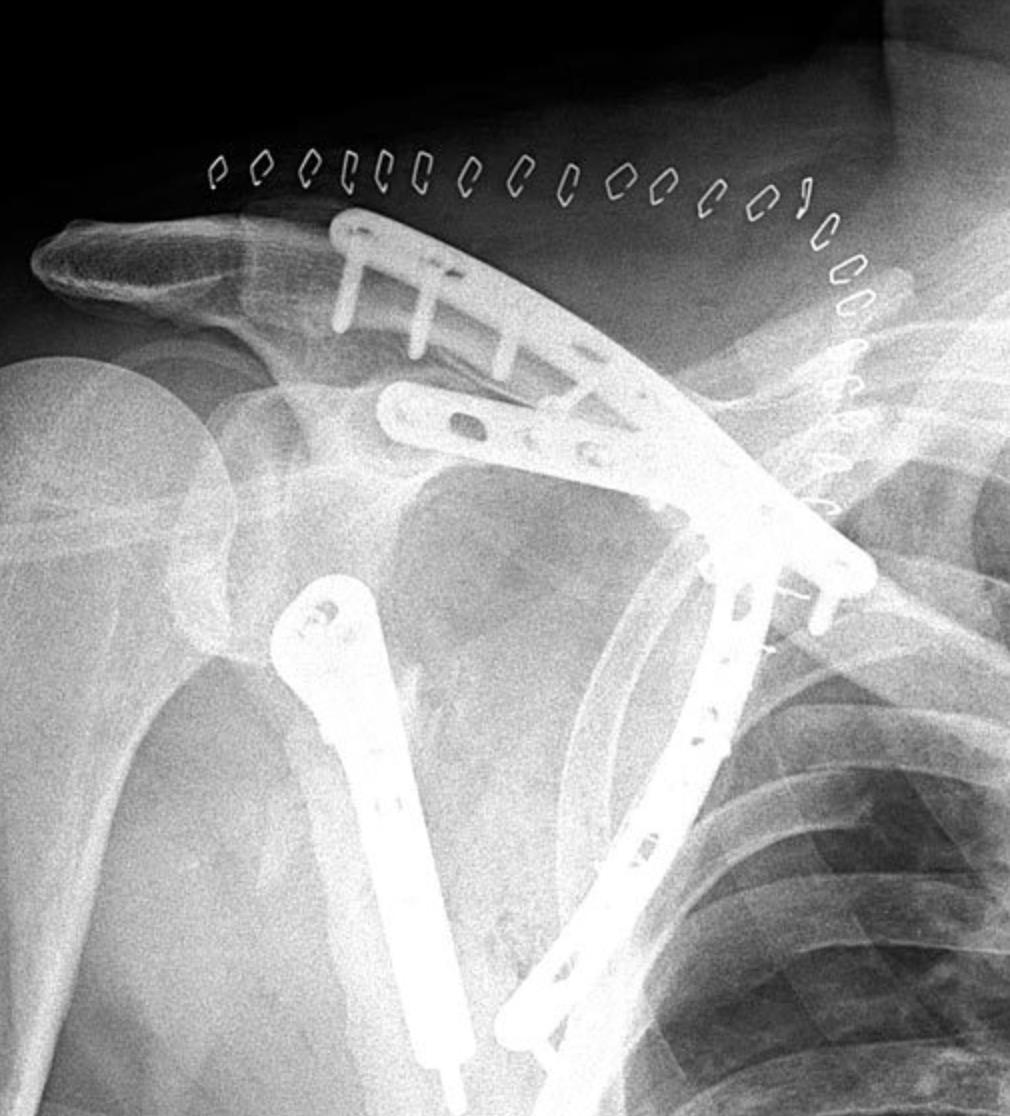

Scapula Plating System

• The Acumed Scapula Plating System offers indication-specific titanium plates that can address challenging fractures of the scapula, including the glenoid, medial and lateral border, acromion, and scapular spine

• The precontoured plates minimize the need for bending while acting as a template for optimal implant placement and guiding screw fixation to osseous regions.